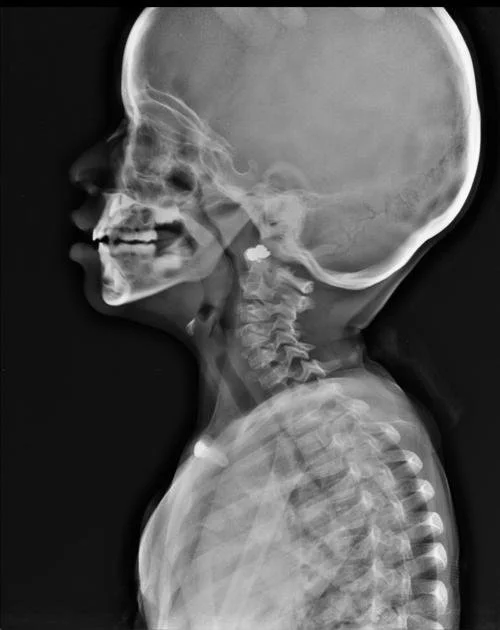

un rayon X des voies respiratoires pour mesurer l’impact des adénoïdes